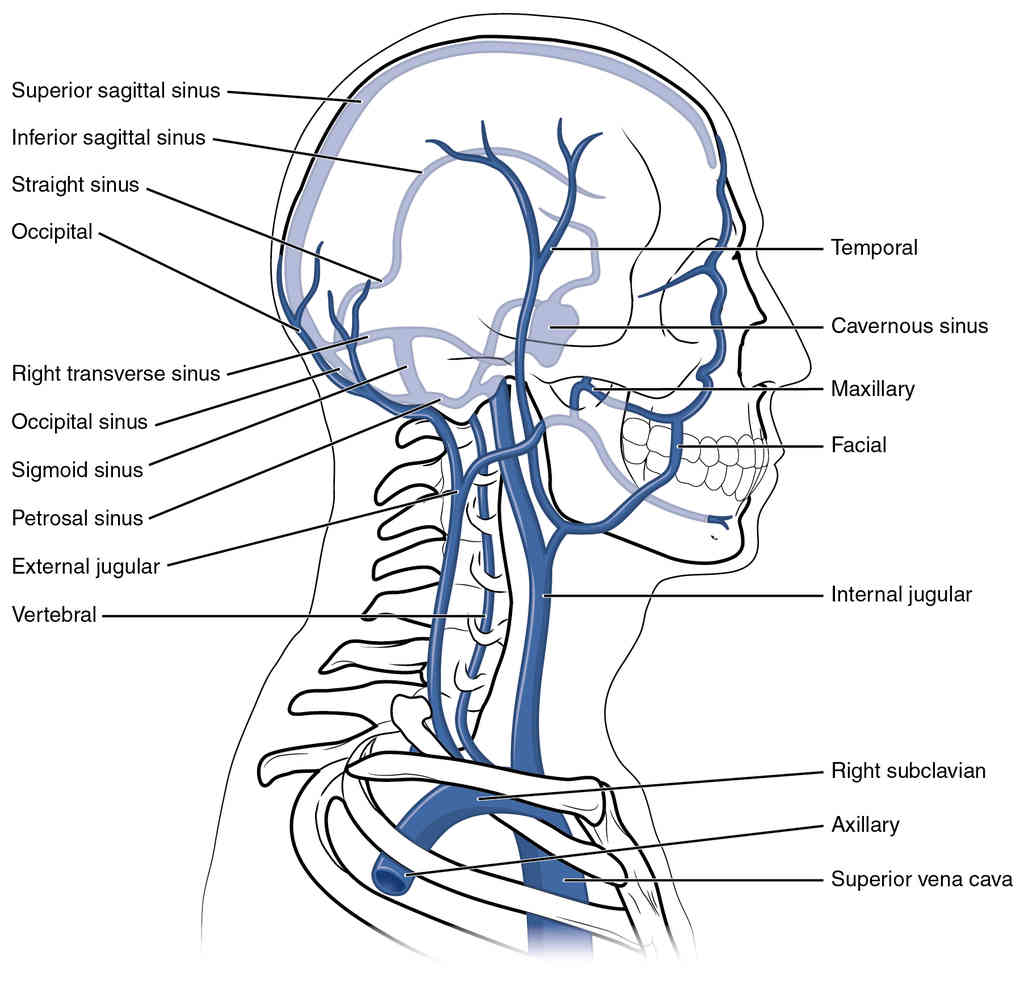

This page is under construction. For now, it is just a resource of the images found in the OpenStax Anatomy and Physiology Handbook. It wil slowly change into a revision tool. Each slide has a number. Use this to refer to the slide. When completed, it will have an unlabelled section, with labelled slides in parallel. On the unlabelled slides, write your answer and use the labelled slide to assess yourself. Keep track by also noting the number on each slide. Improvement at each attempt is important, more so than full marks on a first attempt.